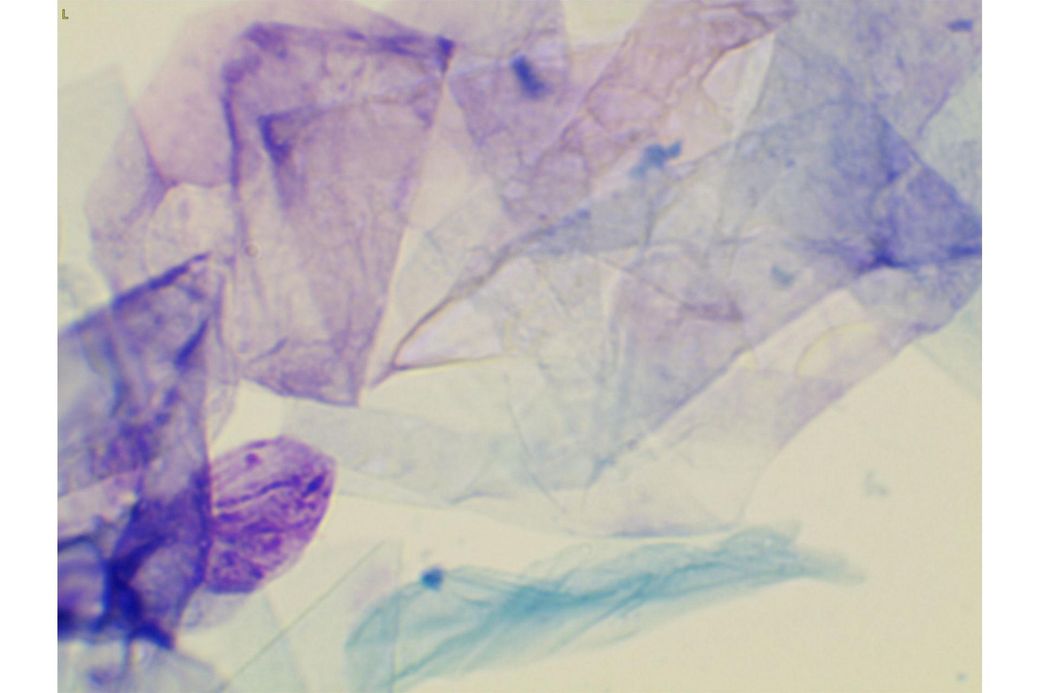

사진만 보고 확진할 수는 없지만 지금 올려주신 귀는 적어도 오른쪽은 정상으로 보이기 어렵습니다 왼쪽은 비교적 연분홍에 가까워 보이지만 오른쪽은 털과 분비물이 많이 차 있고 피부가 자극받은 듯한 모습이라 외이염 가능성을 먼저 생각하게 됩니다 그리고 질문자님이 적어주신 머리 털기 하루 여러 번 귀 만질 때 통증 솜만 닿아도 예민함 귀 긁기 같은 증상은 외이염에서 흔한 신호입니다